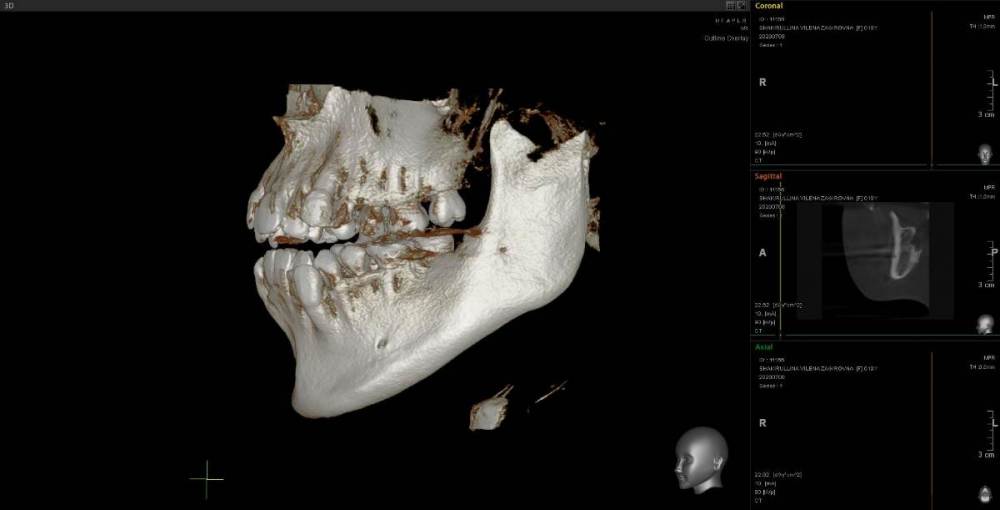

Женька Опубликовано 23 июня, 2021 Поделиться Опубликовано 23 июня, 2021 Коллеги, приветствую. Пришла пациентка с направлением на удаление 1.6-2.6 по ортодонтическим показаниям. Расспросив узнал, что принял решение такое ортодонт, тк премоляры интактны, а вот 1.6 эндодонтически пролечен. 2.6 с пломбой. Вопрос, оправдан ли такой подход? Есть лишь реконструкция КТ. Зубы я конечно не удалил, тк о таком подходе слышу впервые. Связавшись с ортодонтом узнал, что нестандартное удаление... Что думаете? p/s мудрые почему-то пока не удаляем... Ссылка на комментарий